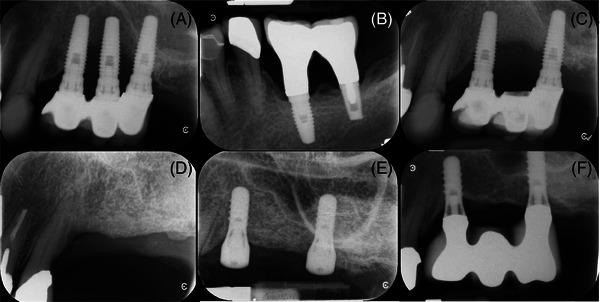

METHODS & RESULTS: We identified four cases in which the middle implant of a 3-IS multiunit FDP suffered advanced bone loss, ultimately leading to implant removal. While more than one possible risk for implant failure existed in each case, a common thread was that the prosthetic platform of the middle implant for all patients was coronally positioned relative to the corresponding mesial and/or distal implants.

我们确定了4例3颗种植体联冠多单位FDP中间种植体出现严重骨吸收,最终导致种植体被取出的病例。虽然每例中存在不止一种可能导致种植体失败的风险因素,但一个共同的情况是,所有患者中间种植体的义齿平台相对于相应的近中种植体和/或远中种植体向冠方移位。